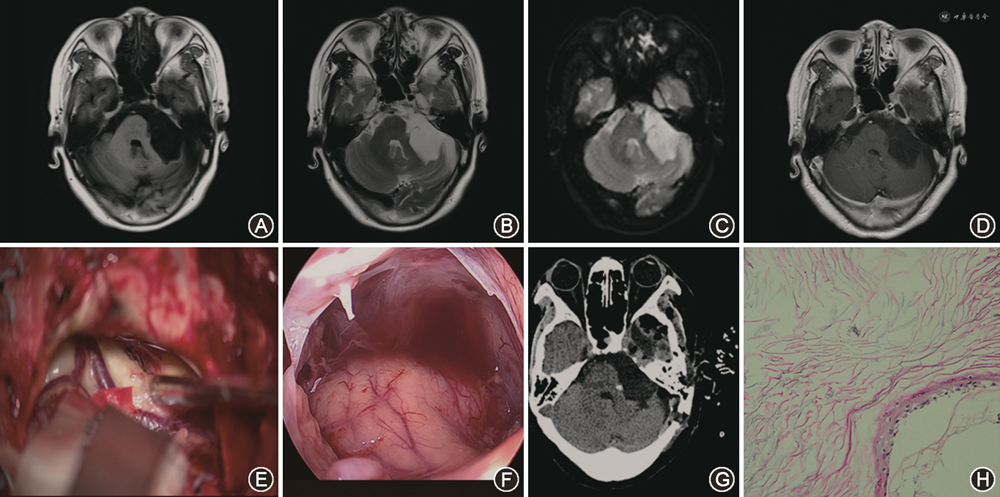

1.手术结果:49例患者均行显微手术切除肿瘤,38例在神经内镜下发现残留肿瘤,并在内镜辅助下进行二次切除,其中仍有5例未全切除。49例患者共全切除44例,次全切除5例。典型病例见图1。

1.对象:回顾性分析2013年1月至2021年1月徐州医科大学附属医院神经外科收治的49例桥小脑角胆脂瘤患者,男27例,女22例。患者年龄12.0~71.0(44.2±1.8)岁,单侧听力下降20例,耳鸣14例,头晕或平衡障碍16例,慢性头痛26例,单侧面部麻木或面部疼痛9例,眼睑痉挛7例,面神经功能House-Brackmann Ⅰ/Ⅱ级38例,Ⅲ/Ⅳ级11例[6]。症状持续时间6~120(17.9±3.4)个月。磁共振成像(MRI)是首选的诊断方法,因为它清楚地显示了肿瘤的位置及其与周围组织的关系[7, 8]。49例患者均进行了MRI扫描,肿瘤在 T1 加权像上为低信号,在 T2 加权像上为高信号,DWI序列呈高信号,增强扫描未发现明显强化[7]。肿瘤大小3.0~7.5(4.1±0.1)cm。11例患者肿瘤向颅中窝扩展;5例患者的肿瘤穿过中线进入对侧;28例患者Ⅴ至Ⅸ颅神经受累,其中1例肿瘤侵及第Ⅹ和 Ⅺ颅神经;12例肿瘤压迫脑干;5例与基底动脉关系密切。本研究符合《赫尔辛基宣言》对伦理的要求,所有患者或其法定代理人均书面签署知情同意研究方案。

2.手术方法:手术均采取侧卧位,三钉头架固定予以乙状窦后入路直切口,具体入路及切口由肿瘤的部位及大小决定。切开皮肤,游离骨窗,上方临近横窦,外侧至乙状窦,打开枕大池释放脑脊液降低颅内压。用自动脑压板牵开小脑组织,可见实质部分呈白色油膏样胆脂瘤,暴露面神经、岩静脉、三叉神经,用显微器械分块切除肿瘤,然后在0°和30°硬性神经内镜辅助下寻找残余肿瘤,继续予以弯头剥离子、吸引器予以吸除,暴露出滑车、外展及基底动脉、大脑后动脉等结构,予以彻底清除肿瘤,创面彻底止血,地塞米松生理盐水从深到浅冲洗手术野及邻近脑池,逐层缝合硬脑膜、肌肉、筋膜及头皮。